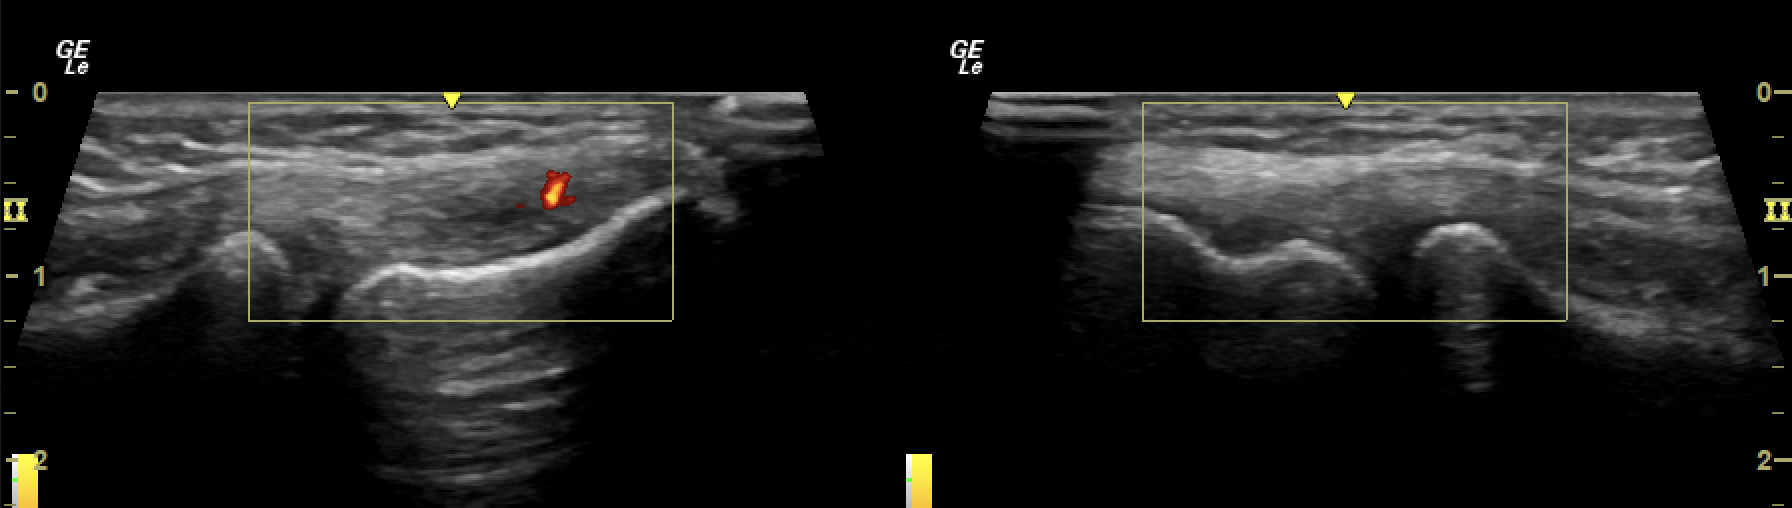

US imaging case - Tennis elbow

3.5 - The MSK playbook; Ultrasound work up for tennis elbow/ golfer’s elbow.